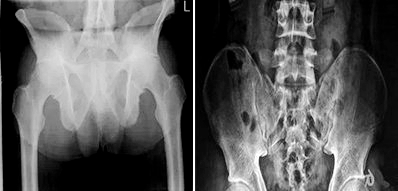

崔丽主任通过与赵先生父子的沟通以及深入检查,检查结果显示:赵先生的强直性脊柱炎已经到了晚期,而小赵的病情较轻,尚属强直早期。

(图:父子两人的CT照对比)

针对父子俩的相关情况,崔丽主任为他们治疗制定了详细的治疗方案。小赵的病情较轻,经过两个疗程的治疗以后,他全身各项功能检查时已显示正常。

而赵先生由于患病时间较长,在经过三个疗程的治疗以后,又接受了一个疗程的巩固治疗,现也已达到了临床康复的标准。